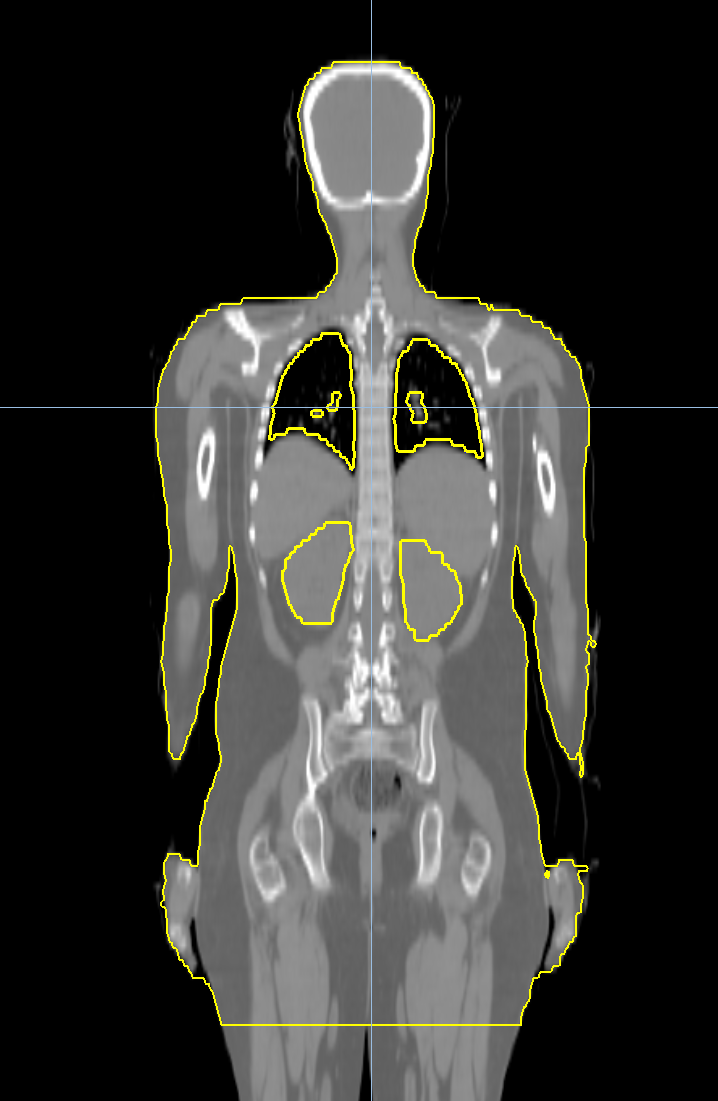

< View All Plan Studies RADIXACT SYSTEM Left Breast with Deep Inspiration Breath Hold Case History AGE: 76-year-oldGENDER: Male Medical History Immidiate tolerance: Grade II dermatitis with eyelid edema, Grade I conjunctivitis resolved with Sterdex Diagnosis: Squamous cell carcinoma of the right lower eyelid Planning CT Images Treatment Plan Images